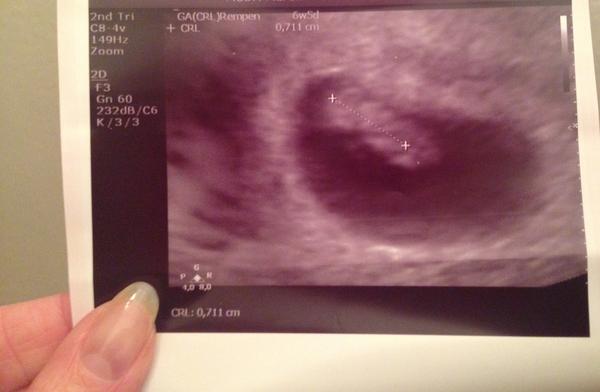

my mame aj prvu fotienku 💞

Ahojte..tak moje prvé sono dnes dopadlo tak že..som 6 tt+ 5 a mame 8 mm 🙂 pevne verim,ze kazda z nas to tu dobojujeme az do konca 👣🍼